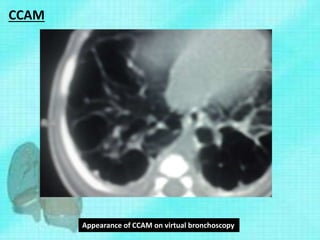

• Other diagnostic means include (MRI) and

Bronchoscopy.

• One of the most recent developments in the

area is virtual bronchoscopy (VB).

• VB is a non-invasive three-dimensional (3D)

technique that uses multidetector CT-generated

image.

• It can evaluate the airways down to the sixth- to

seventh-generation bronchial subdivisions

Appearance of CCAM on virtual bronchoscopy